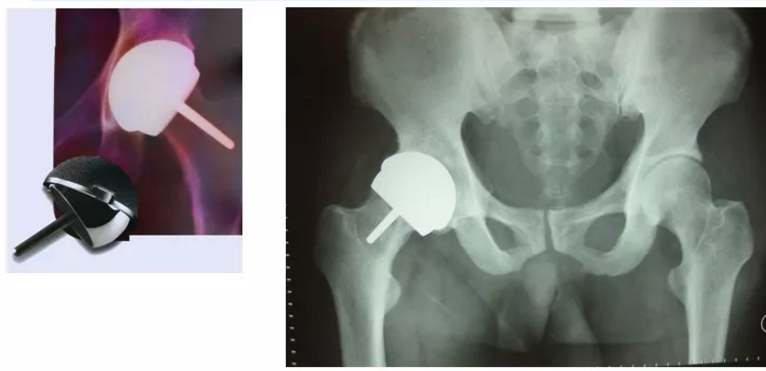

半髋关节:

单极头

双极头

髋关节表面置换:

使用双极头还是单极头

- 临床上最常用的人工股骨头为Moore型和Thompson型

- 临床研究表明,双极头磨损再手术率低于单极头,但是研究同时发现超过85岁老年股骨颈骨折使用单极头在效果,并发症方面与双极头无差别。因此在欧洲及香港,单极头仍被高龄病人使用。